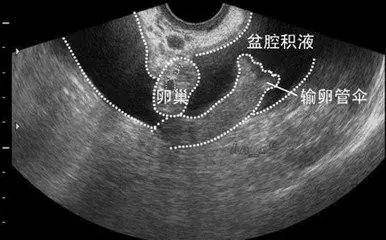

患有阴道炎,宫颈炎时,炎症上行感染,最终也可能导致盆腔炎,形成积液.